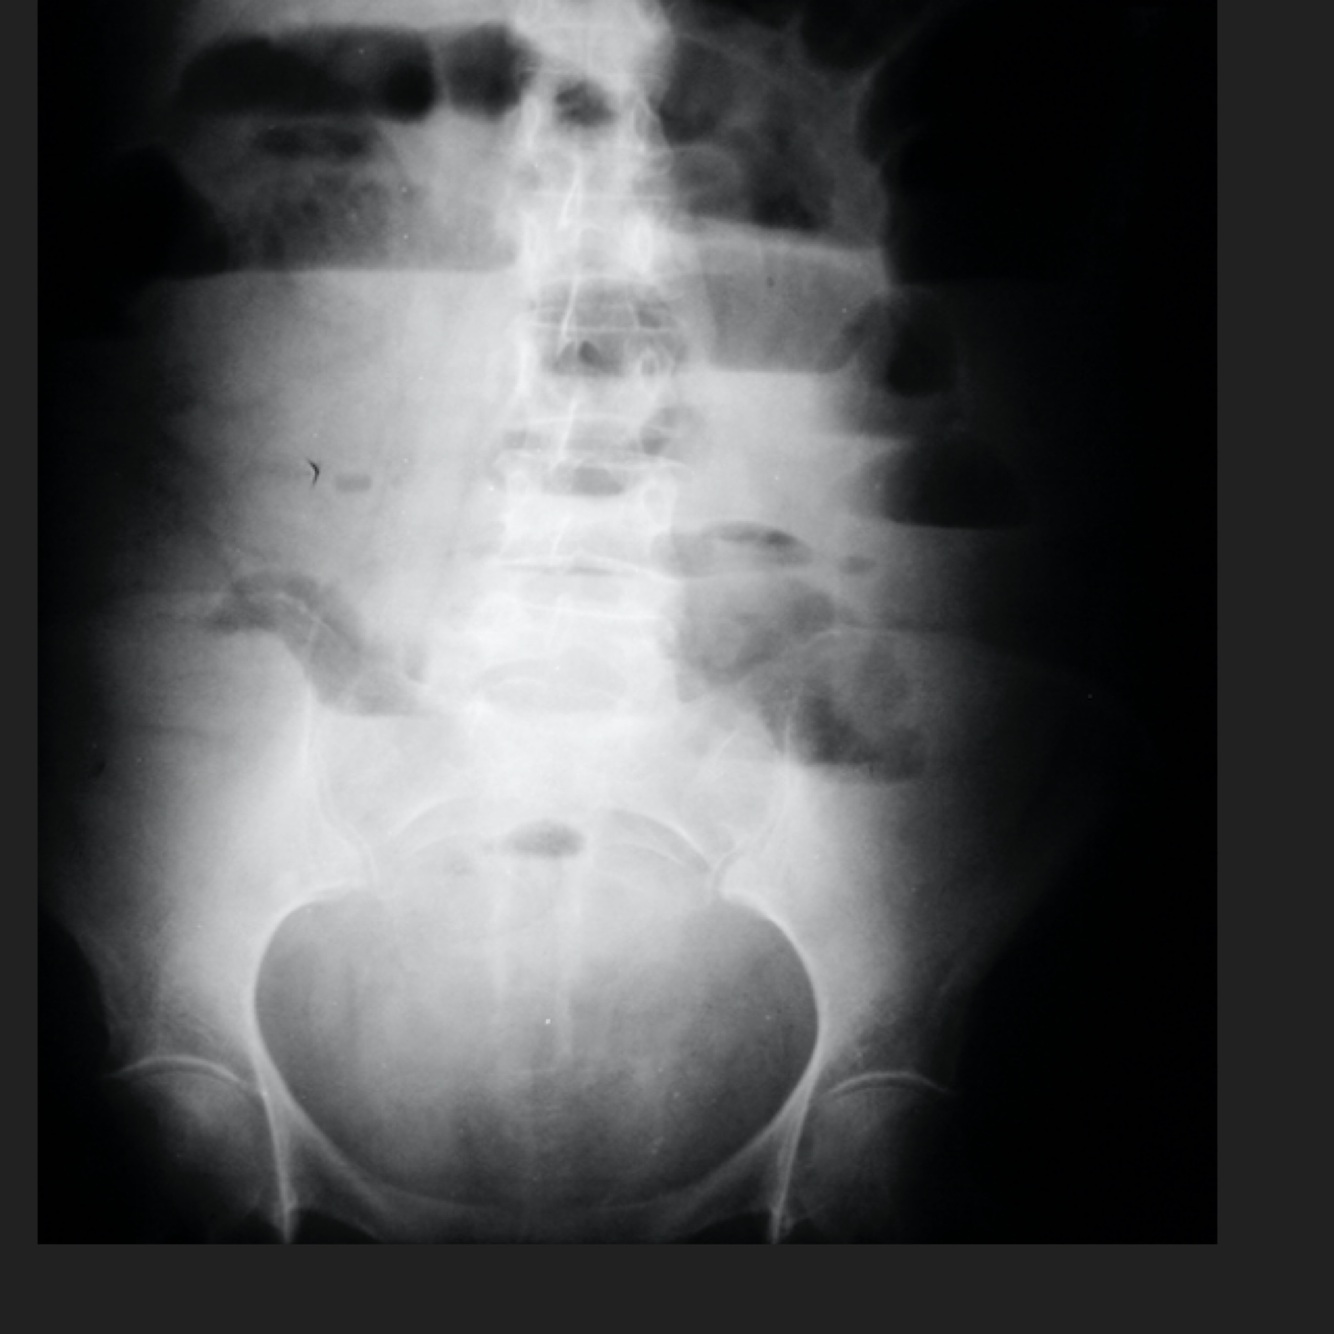

Q

Causa de la insuficiencia renal del paciente

A

Nefrocalcinosis